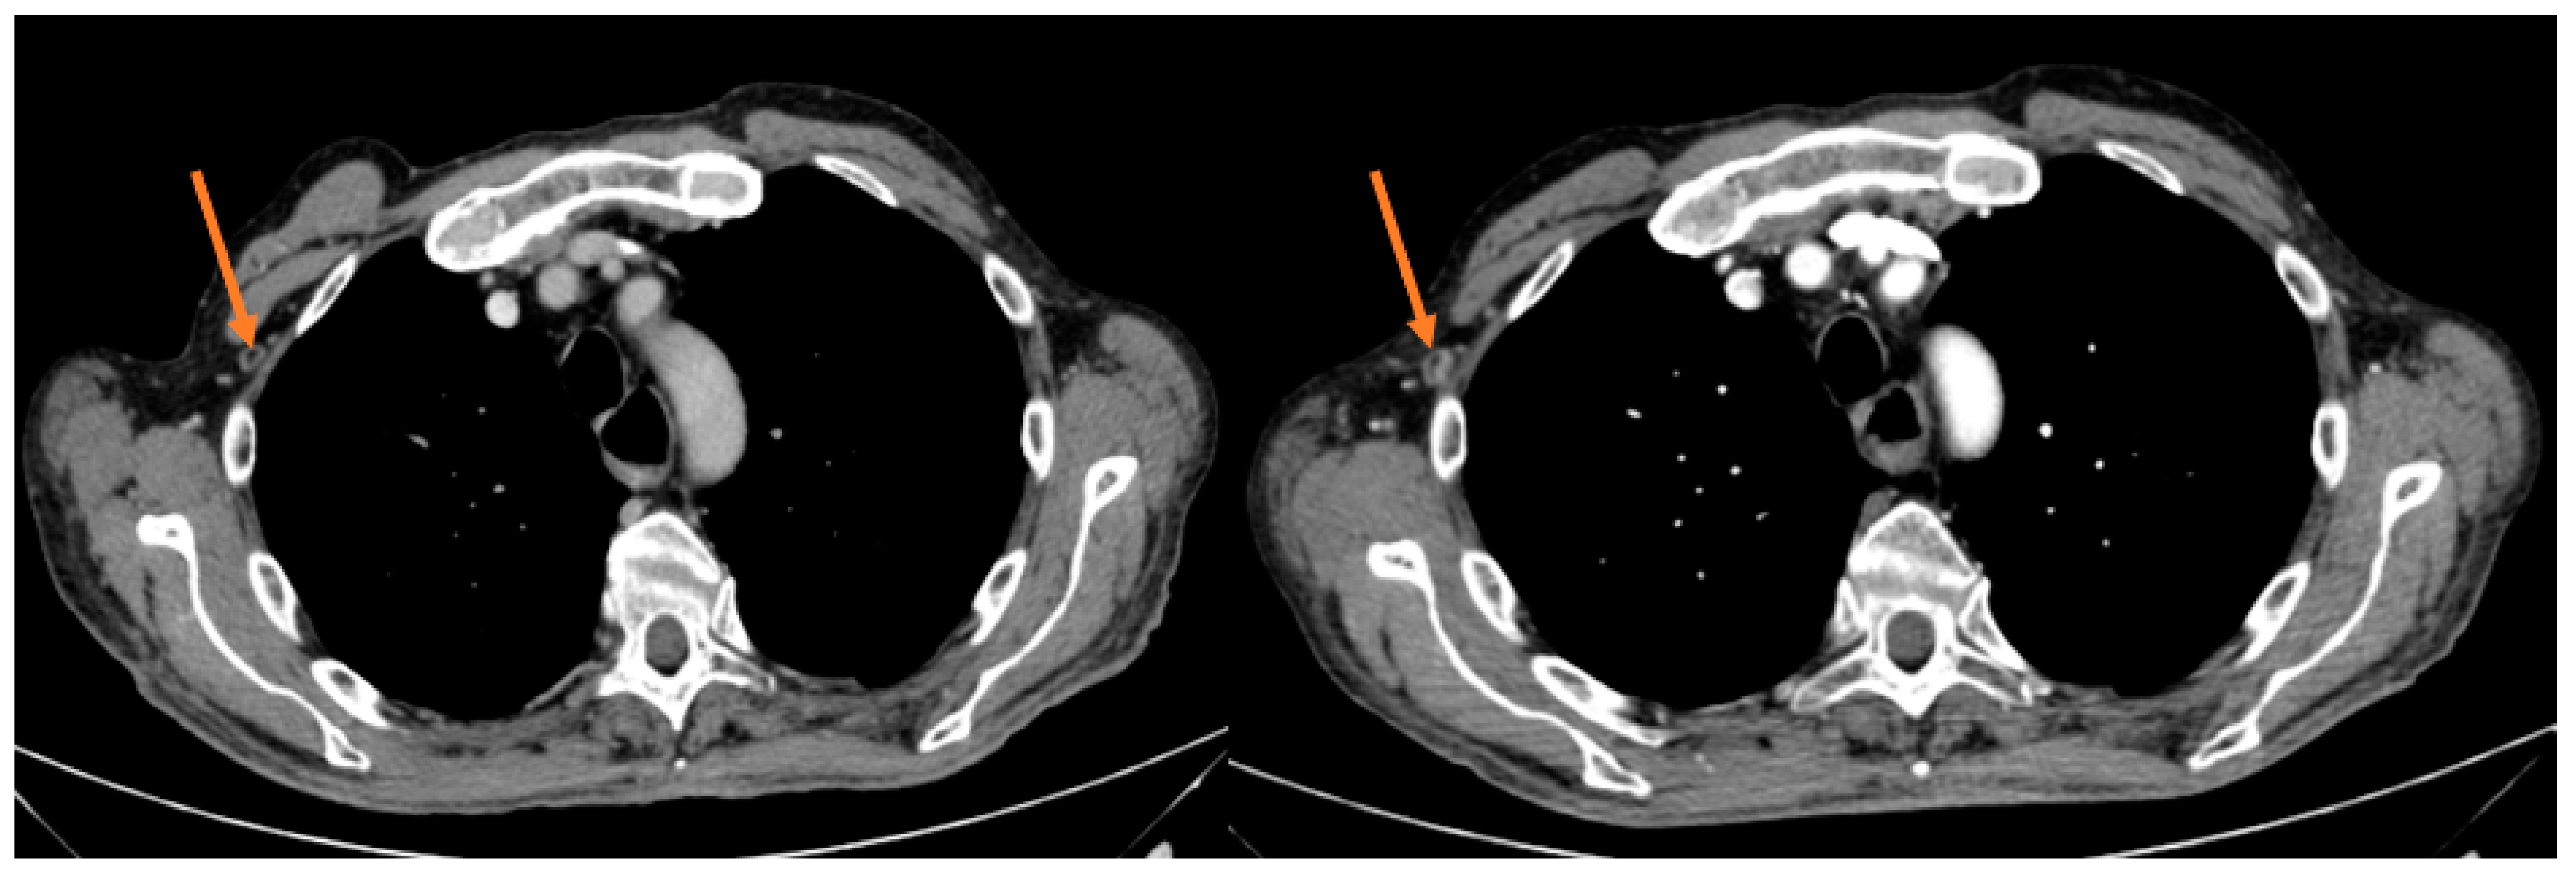

| Partial response | 1 | 12.50% |

| Stable disease | 1 | 12.50% |

| Progression disease | 6 | 75 |